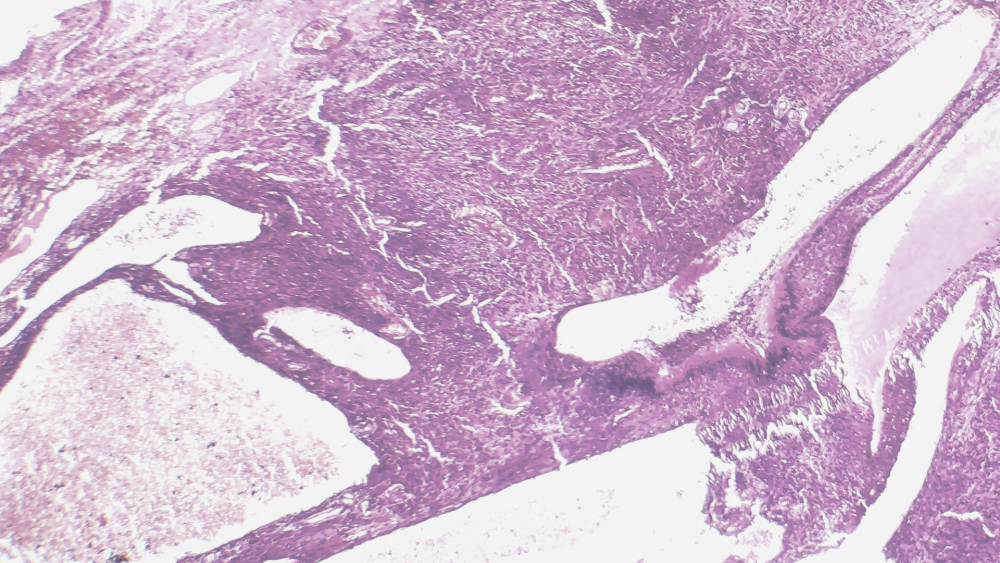

Саркомы мягких тканей головы и шеи

Саркома мягких тканей (СМТ) — это злокачественное новообразование, развивающееся из клеток внескелетной соединительной ткани, к которой относятся все анатомические образования между скелетом и кожей: мышцы, жировая ткань, сухожилия, связки и т. д.).